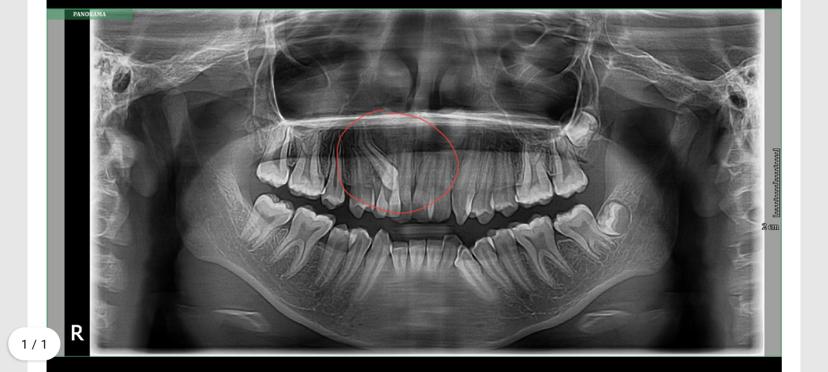

Cyst